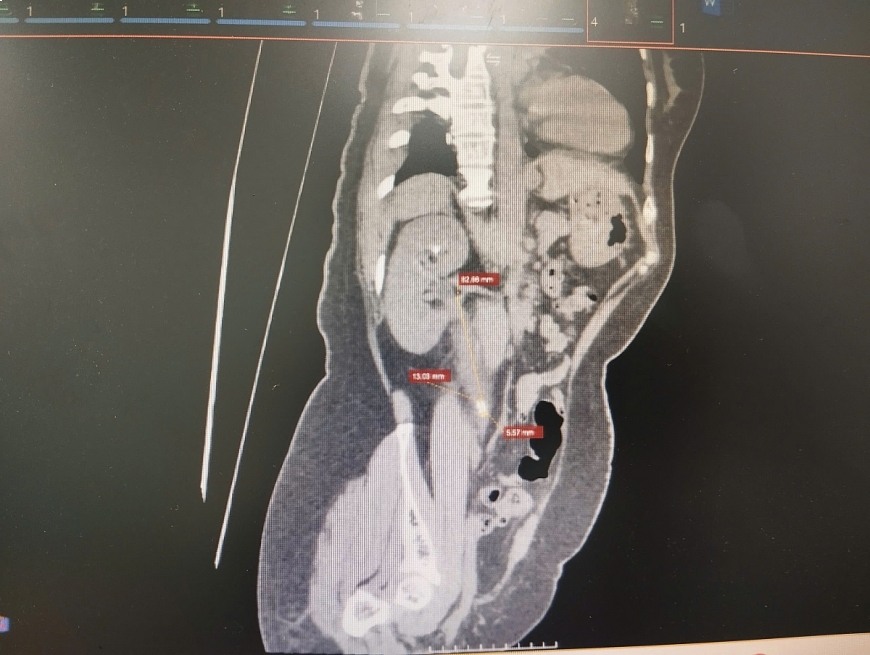

도르니에 툴리오 고출력 레이저 시스템과 결합된 연성 내시경 기술을 숙달함으로써 하노이 국립대학교 의과대학 병원(린담 시설) 비뇨기과, 남성학 및 성 의학과 의사들은 47세 환자(하노이 동응악 거주)가 단 한 번의 시술로 다발성 결석을 깨끗하게 제거하는 데 도움을 주었습니다.

주목할 만한 점은 Dornier Thulio 레이저 시스템이 Thulium 및 Holmium 두 가지 기술을 통합하여 요관 결석을 분해하고 동시에 한 번의 시술로 신장의 결석을 처리할 수 있다는 것입니다.